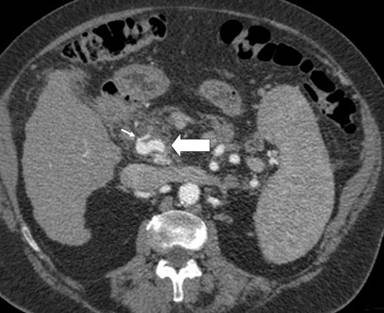

A 75-year-old female performed a quadriphasic abdominal CT examination for the characterization of a focal hepatic lesion, previously identified with a transabdominal ultrasound. Patient had a chronic HCV infection. The physical examination was substantially negative: particularly, the patient did not show any sign or symptom related to the pancreatic arteriovenous malformation or to gastrointestinal bleeding. The MDCT showed a hypervascular area of 3.5x2.5 cm in the pancreatic head, constituted of ectasic vessels (Figure 1); no calcifications were seen inside the mass. The lesion did not determine mass effect or dilation of the main pancreatic duct. During the arterial phase, there was also an early filling of the portal vein and the proximal portion of the superior mesenteric vein. Para-coronal maximum intensity projection and 3D electronic reconstructions made possible to identify the arterial afferents to the malformation (Figure 2), constituted by small aberrant branches from left gastric artery (Figure 3) and posterior inferior pancreaticoduodenal artery (Figure 4); it was also possible to identify the venous efferent drainage, constitute by the portal vein (Figure 5) and the superior mesenteric vein (Figure 6). Other MDCT findings were: presence of a cirrhotic liver with a solid 3.0x2.5 cm mass in the II segment, hyperdense in the arterial phase with washout during the portal phase, referable to hepatocellular carcinoma; an aberrant replacing right hepatic artery arising from the superior mesenteric artery; and a 1.5 cm solid hypodense lesion in the pancreatic body, with fat density and without contrast enhancement, referable to pancreatic lypomatosis.

Figure 4. Arterial phase axial image shows the pancreatic arteriovenous malformation (solid arrow) and its afferent (short arrow) arising from posterior inferior pancreaticoduodenal artery. |